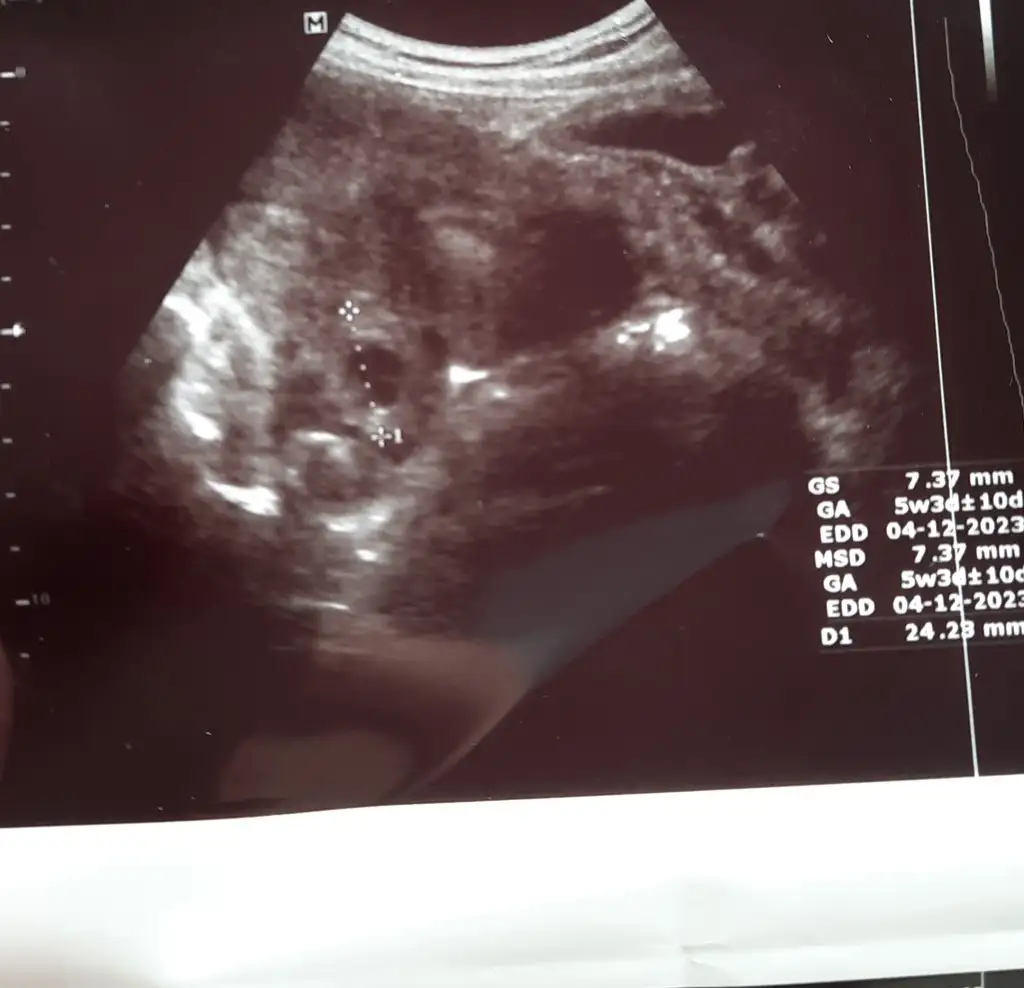

Bana da yorum yapar mısınız kızlar 5+3 günlügüz